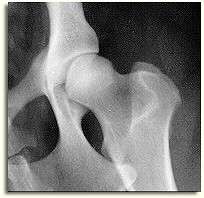

It is especially important to perform a Distraction Index (DI) on dogs that have normal appearing hips on the ventrodorsal extended view, such as appears to be the case in the image on the right. Dogs that are diagnosed as having excellent hips on the traditional VD view can actually have a huge amount of laxity. PennHIP's recommendation is to limit breeding to those dogs that have normal appearing hips on the VD hip extended view and that also have a DI at the breed's mean laxity or tighter.

Luxation means dislocation. A luxated hip is one that has extreme laxity such that it displays dislocation of the two bones of the joint. The x-ray image at the top right of this page demonstrates a fully luxated hip on the right side of the image.

Subluxation means a partial dislocation of two joint members. The x-ray image at the top right of this page demonstrates a subluxated hip on the left side of the image.